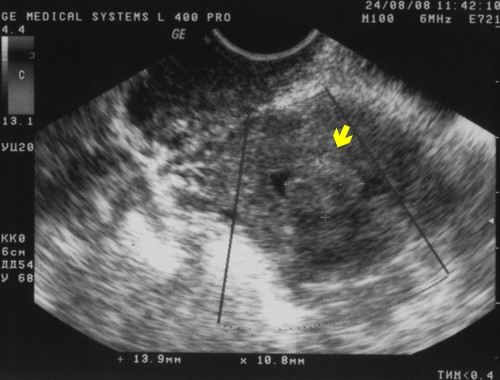

В диагностических целях также используется магнитная и компьютерная томография. УЗИ при помощи трансвагинального датчика дает возможность выявить различные патологии репродуктивных органов женщин, в том числе и аднексит.